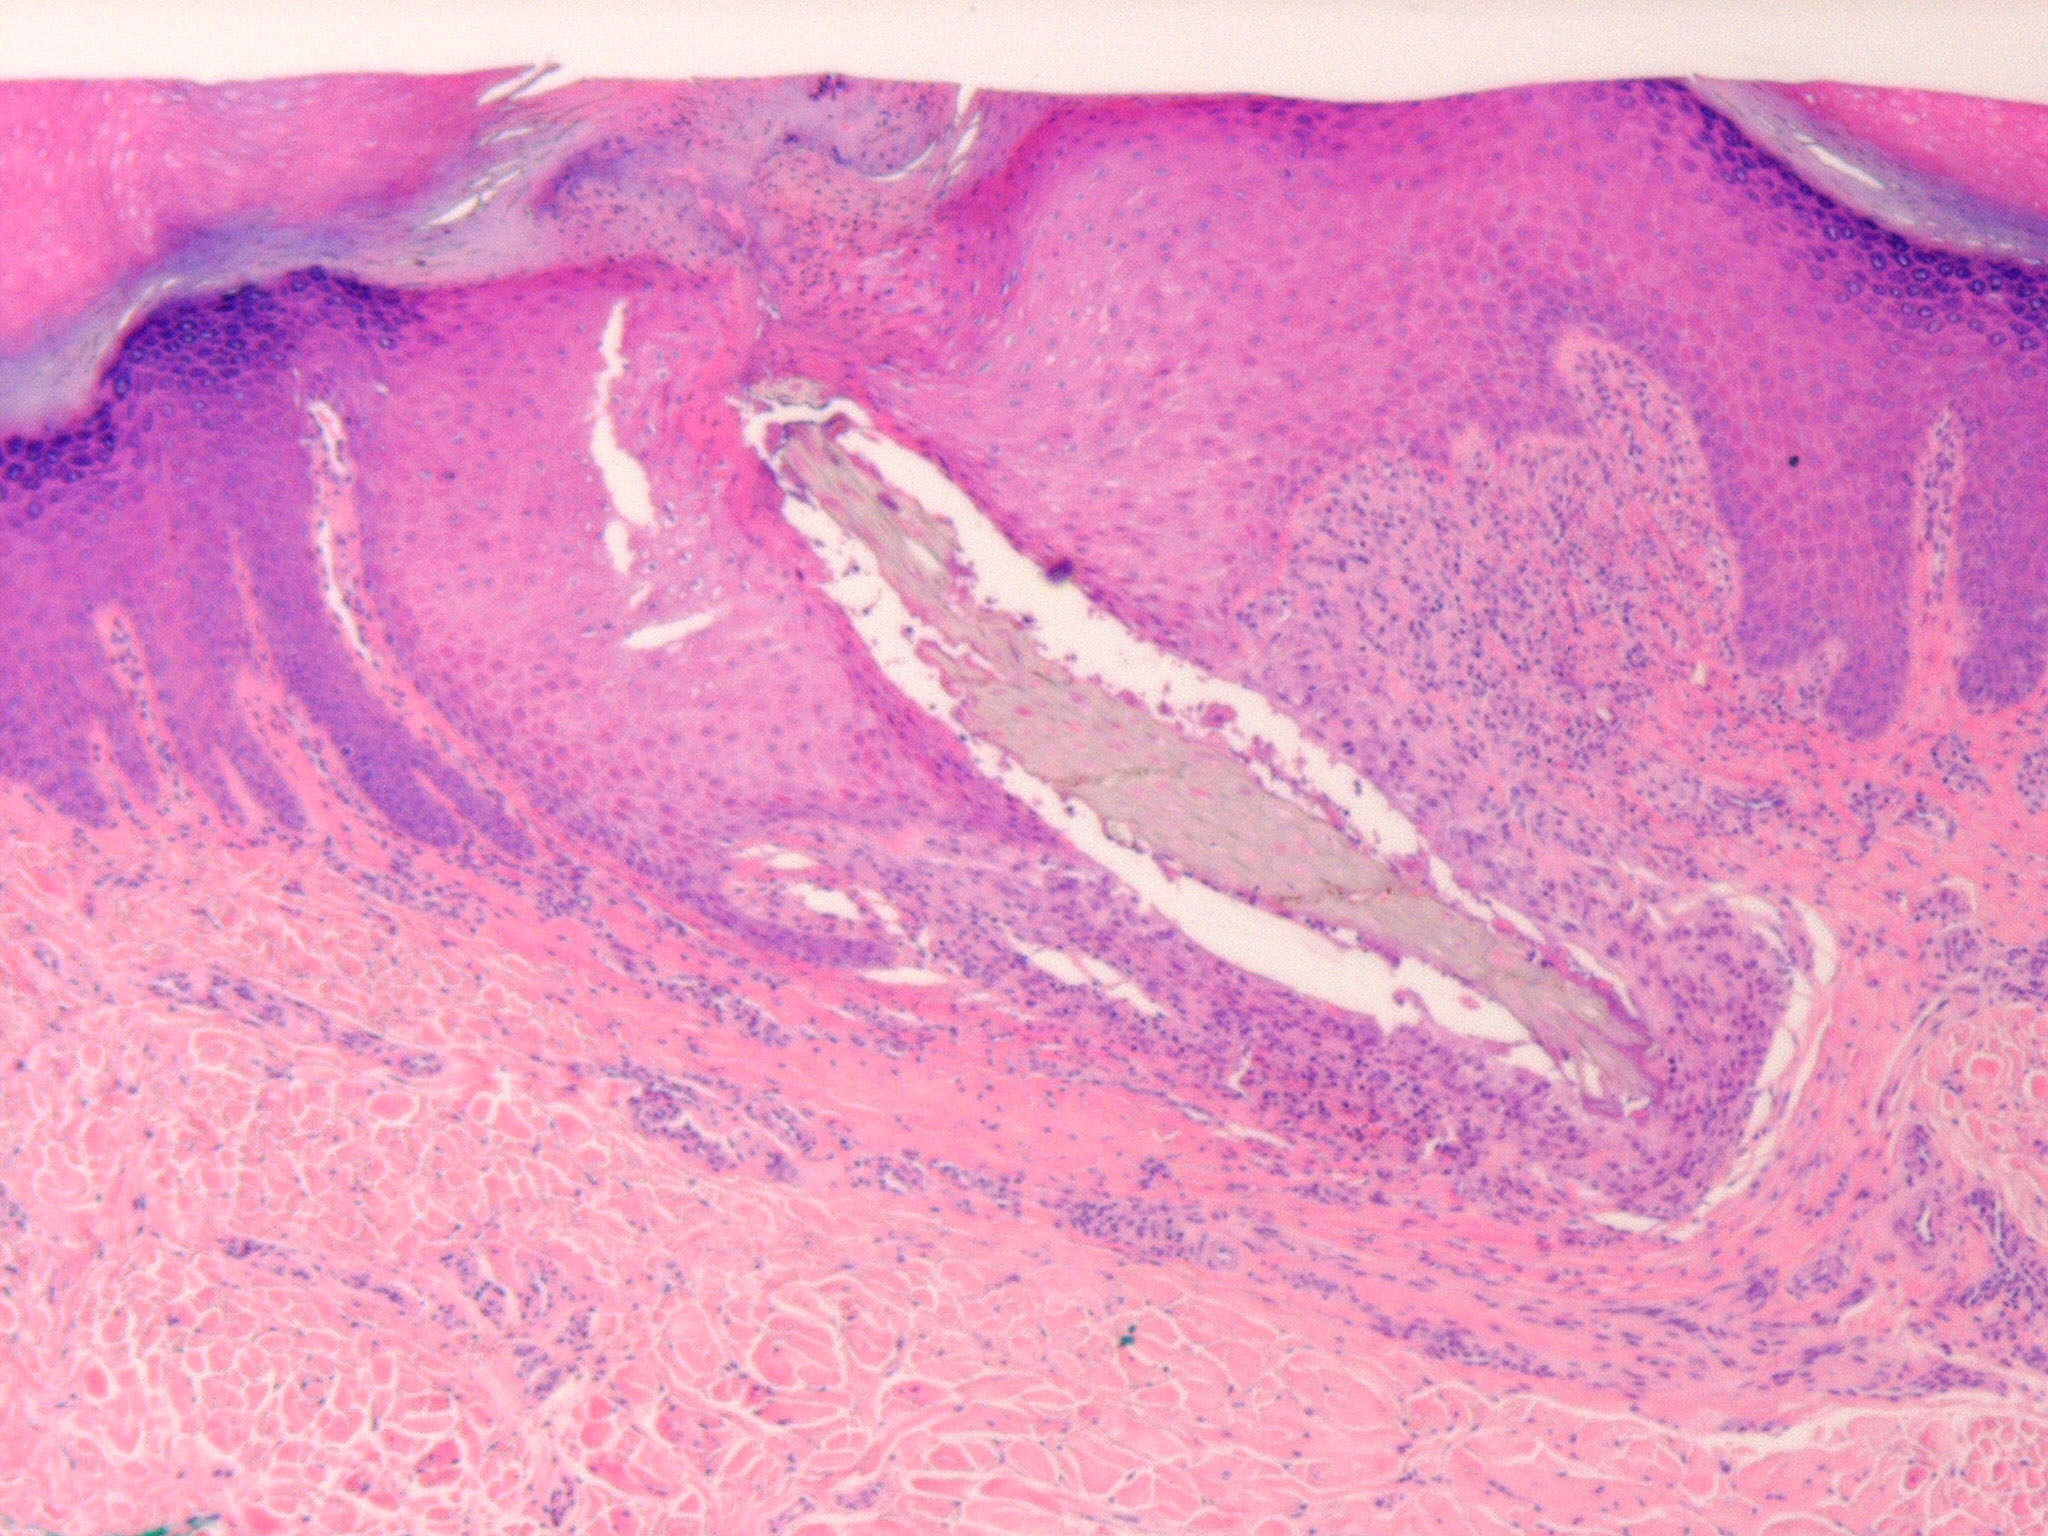

Splinter hemorrhage = النزف المتشظي

OLYMPUS DIGITAL CAMERA